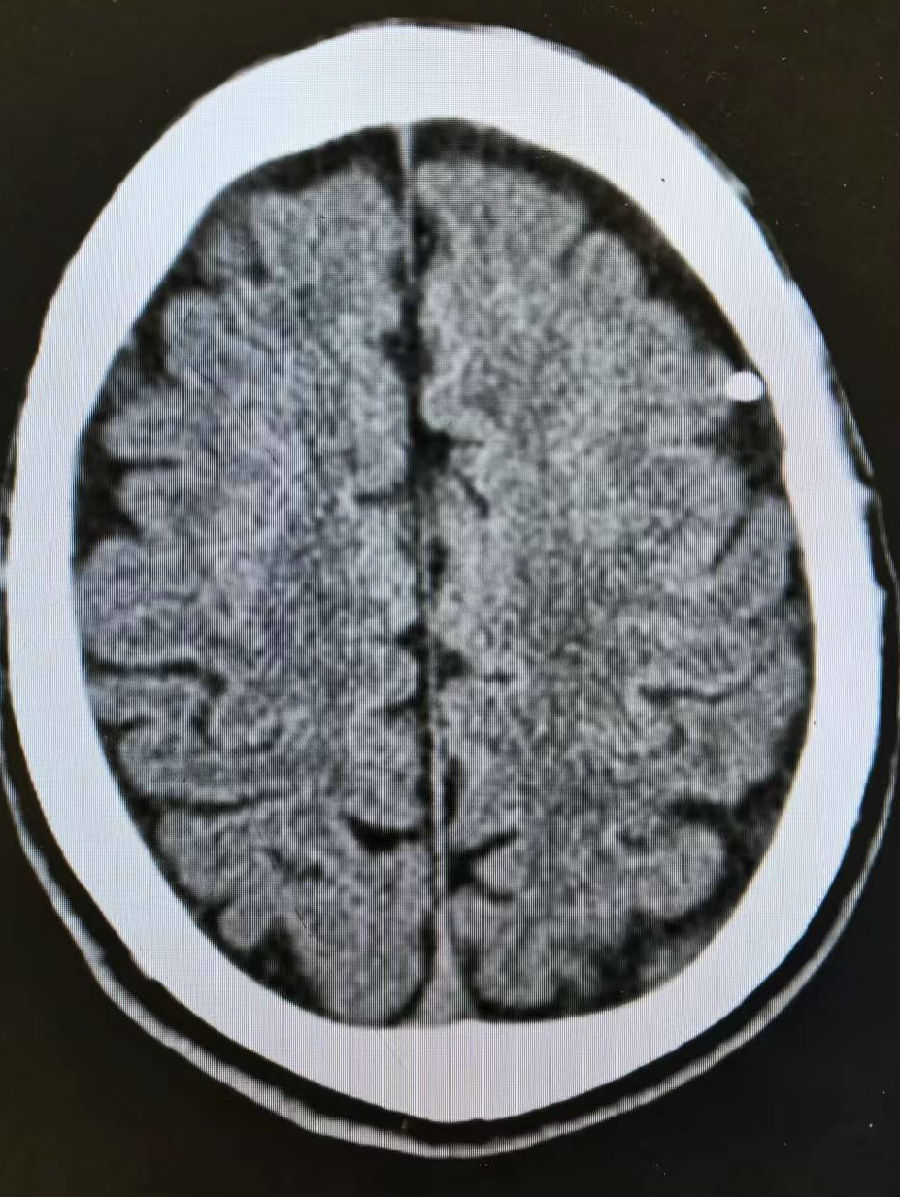

直至最后一次发作后伴有持续头晕,白师傅在家人的陪同下来到我院神经外科就诊。这一来,揭开了疾病的真相。经过详细问诊和系统检查,影像结果让医生和患者本人都大吃一惊:其颅内左额部清晰可见一条状致密金属异物影,深深嵌入脑组织。神经外科副主任张伟立即组织科室深入讨论,结合脑电图定位,明确诊断:正是这枚由颅骨刺入、已抵达左侧额叶皮层的异物,导致了白师傅的癫痫发作。额颞叶皮层是大脑功能区,异物长期存留如同持续刺激“电路”,引发异常放电,这便是癫痫反复发作的根源。